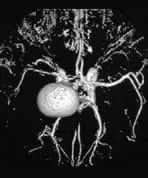

Right Internal Carotid Artery Aneurysm

A patient presents with longstanding headaches.

Findings

A contrast enhanced 3DTOF MRA with post processing reformatted images demonstrates a large right supraclinoid aneurysm. The entering and exiting vessels lie at the anterior aspect of the aneurysm.